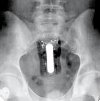

Хирургическое удаление инородного тела прямой кишки. Хирургические вмешательства по удалению посторонних предметов и устранению повреждений кишечника. Хирургическое удаление инородных тел из прямой кишки показано в случае невозможности их малоинвазивного (ручного, эндоскопического, инструментального) удаления, а также в случаях миграции по желудочно-кишечному тракту, повреждения кишечной стенки с развитием кровотечений, перитонита, абсцесса, свища Операция может включать в себя операции лапаротомия с ручным удалением и трансаннеальным удалением объекта без вскрытия кишечной полости; для перфорации - ушивание полости, наложение временной сигмостомии, дезинфекция и дренирование брюшной полости.

Удаление инородного тела прямой кишки через ректоскоп представляет собой неоперативное эндоскопическое удаление инородного объекта из терминальных отделов кишечника через трубку ректоскопа. Эндоскопическое удаление инородных тел прямой кишки показано при небольших предметах, их свободное расположение в прямой кишке и отсутствие признаков перфорации. Это выполняется с использованием различных инструментов (катетер Фолея, зажим, пинцет, пинцет, вакуумный экстрактор ) После введения ректоскопа в просвет прямой кишки под местной анестезией, у детей под общей анестезией. При перфорации кишечника или кровотечении показана экстренная операция.